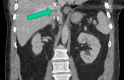

Figure 2. Coronal view of IVC filter in intrahepatic IVC

IVC: Inferior Vena Cava